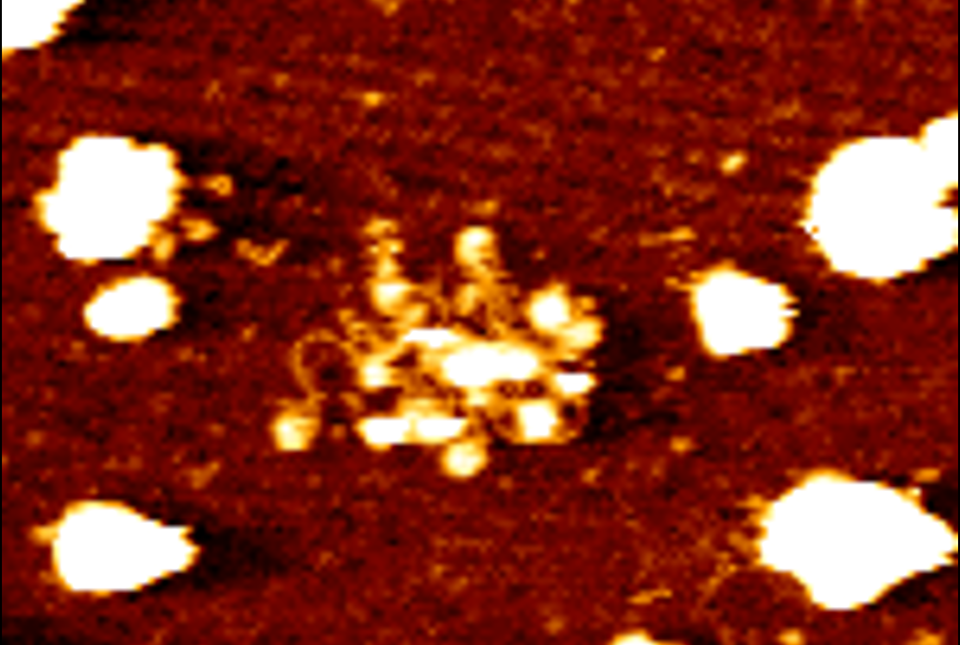

In the study, reported Dec. 3 in Nature Cancer, the researchers examined cancer cells’ secretion of short stretches of DNA packaged on tiny capsules called extracellular vesicles (EVs). All cells use EVs to secrete proteins, DNA and other molecules, and tumor cells are particularly active EV secretors. The biological functions of these EV-packaged molecules are still being explored, but in this case, the researchers discovered that in various cancer types, EV-DNA secreted by tumor cells works as a “danger” signal that activates an anti-tumor response in the liver, reducing the risk of liver metastasis.

“We had assumed that this DNA is in the form of ‘naked’ strands inside EVs, but we were surprised to find that it is mostly on the EV surface, wrapped around support proteins called histones, much as it would be in a chromosome,” said Dr. Wortzel.